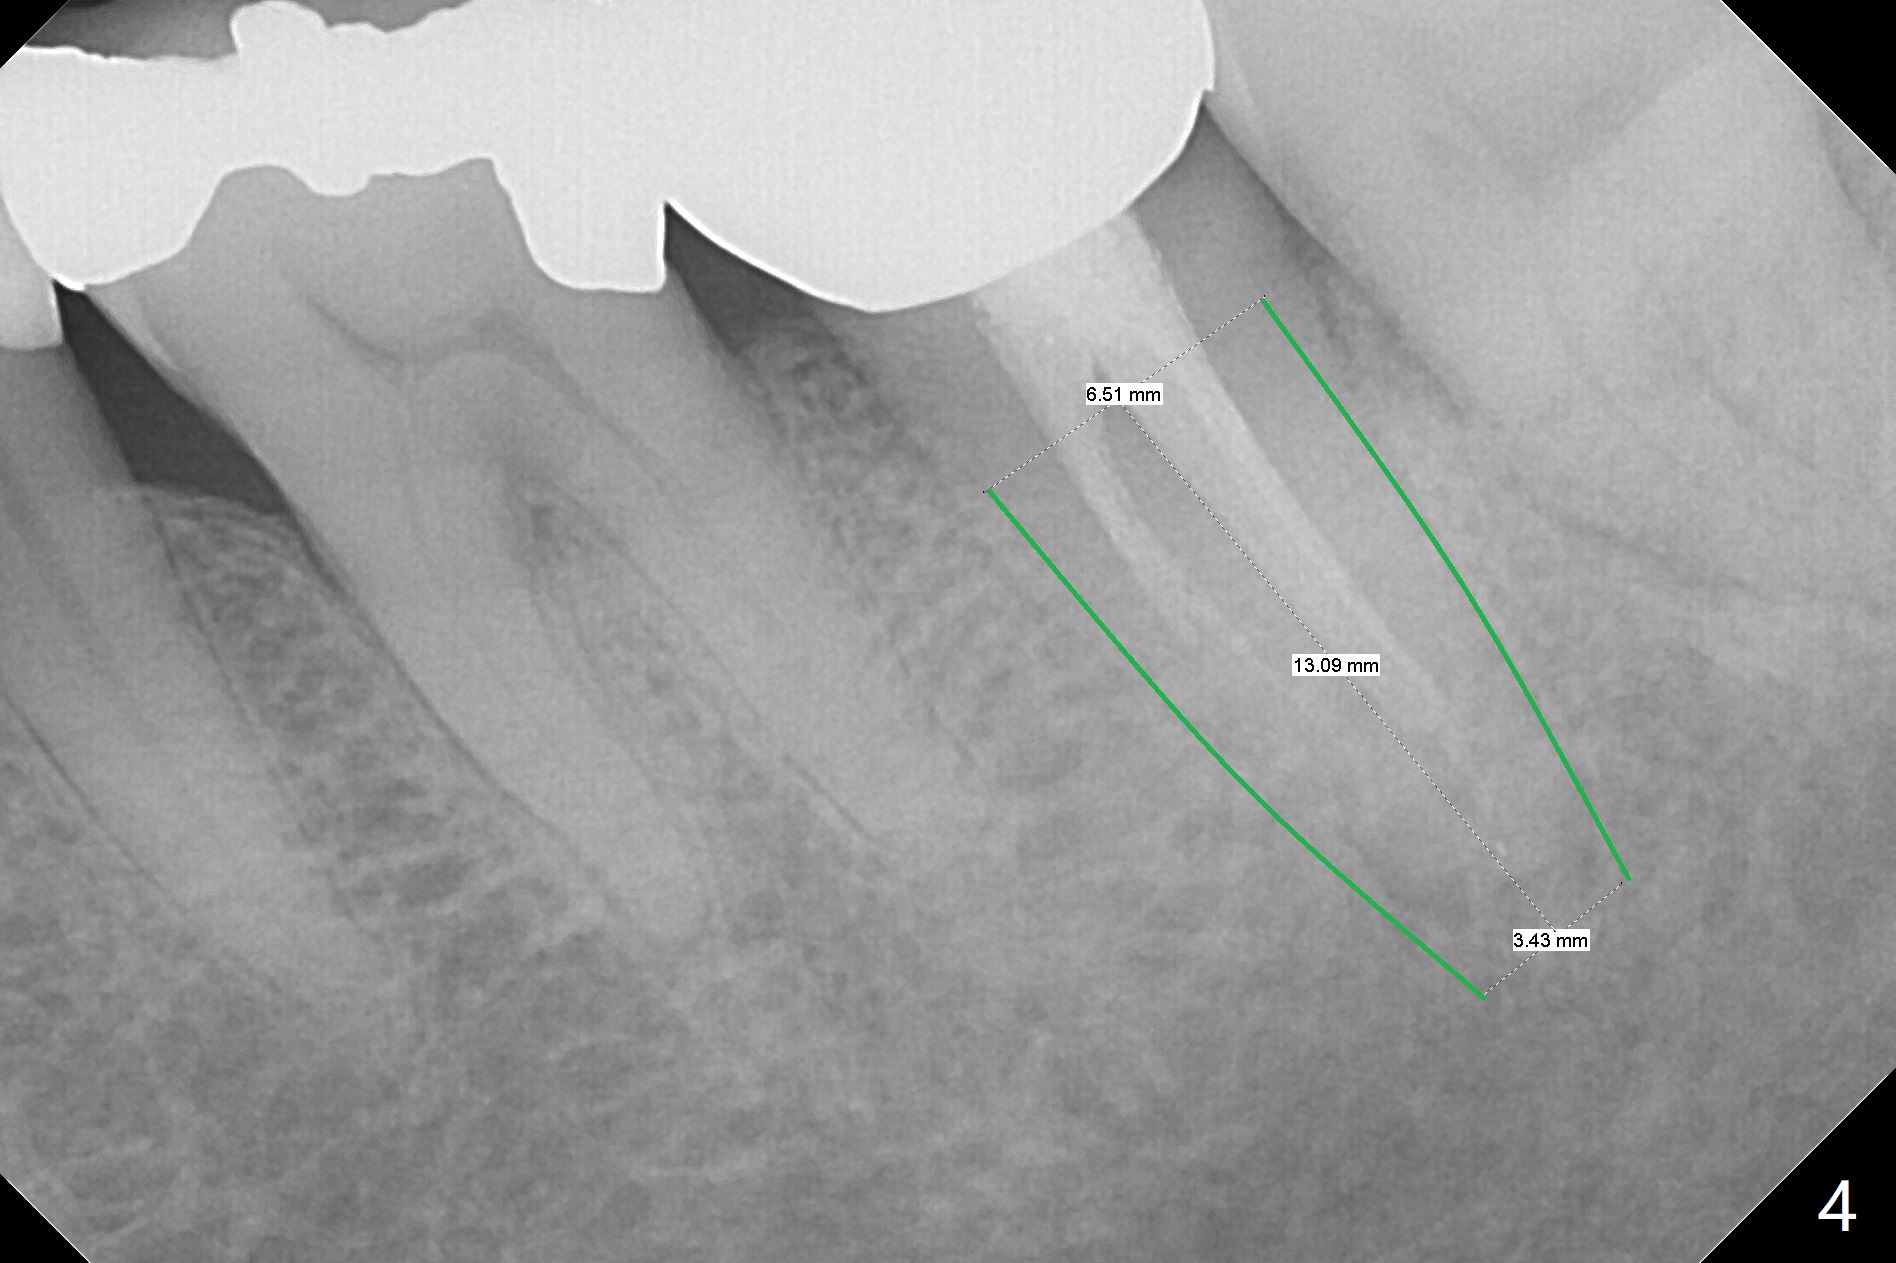

In all, the patient should be a heavy bruxer. When extraction and immediate implant is done at #18, immediate provisional should be low and stable (keep bone graft in place). It appears that a temporary abutment can accomplish the purpose. An IS one has been trimmed. There are 2 options for implant placement: along the long axis of the socket (Fig.4 using taps for osteotomy) and in the mesial slope of the socket (Fig.5 using drills). If the bone level implant (tap) does not work, switch to tissue level one (Fig.6).